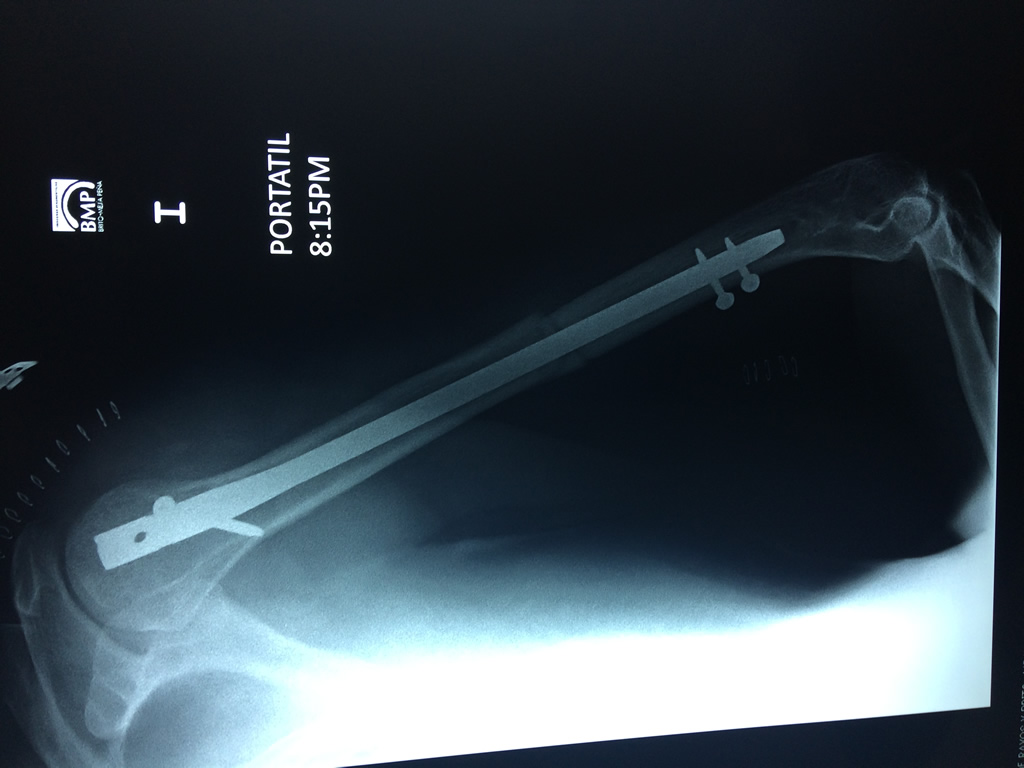

Cirugias en El Salvador - Húmero

El Húmero (en latín, humerus) es el hueso más largo de las extremidades superiores en el ser humano. Forma parte del esqueleto apendicular superior y está ubicado en la región del brazo. ... El extremo proximal del húmero tiene la cabeza, cuellos quirúrgico y anatómico y tubérculos mayor y menor.